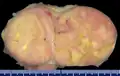

Micrograph of a solitary fibrous tumor. H&E stain.